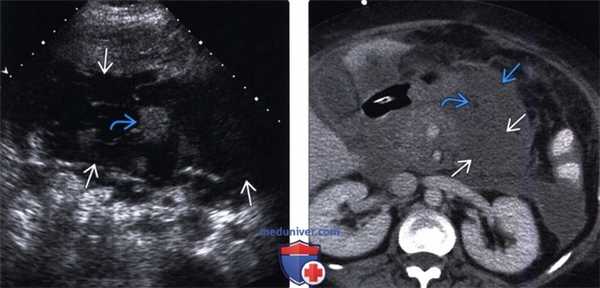

(Левый) На поперечном срединном УЗ срезе в ложе поджелудочной железы определяется гетерогенное скопление, содержащее нежидкостные фрагменты, что указывает на развитие некроза поджелудочной железы и перипанкреатических тканей.

(Правый) У этого же пациента при КТ с контрастным усилением на поперечной томограмме наблюдается полное отсутствие контрастирования тела и хвоста поджелудочной железы, что характерно для панкреонекроза. Также определяется пери панкреатическое скопление жидкости, содержащее нежидкостные фрагменты, это указывает на острый некроз перипанкреатических тканей и формирование очага острого некроза.